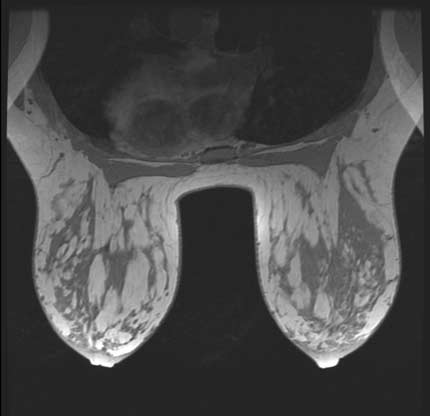

También utilizamos la RM para el control de prótesis mamaria y valorar una posible disfunción de la misma.